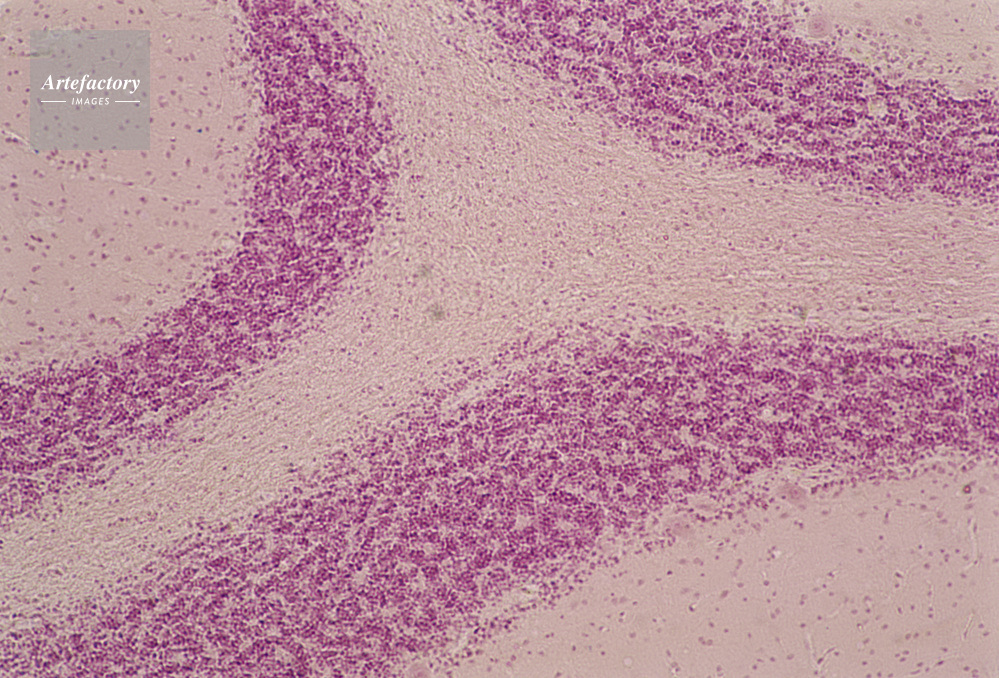

| キャプション | 小脳組織,100倍 | 制限事項 | ||